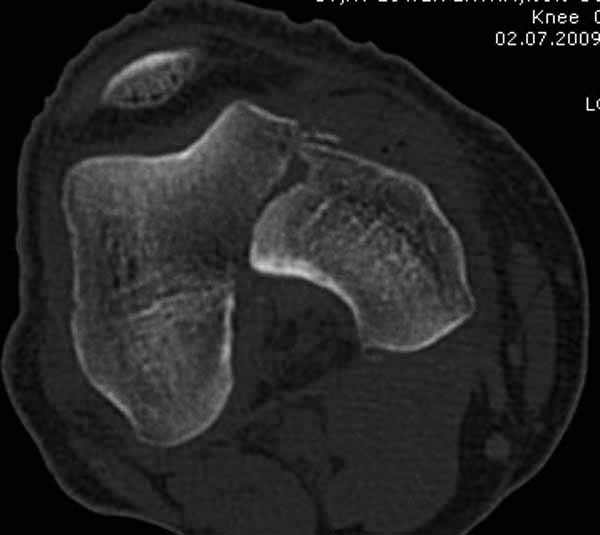

Однако в случае, представленном Константином Никитиным, не может быть применён ни ретроградный ни антеградный остеосинтез. Причина - нереально выполнить вышеуказанные необходимые требования, касающиеся дистальных блокирующих винтов. Из-за низкого перелома латерального мыщелка (перелом Hoffa) невозможно через него провести хотя бы 2 блокирующих винта, поскольку линия перелома мыщелка расположена либо на уровне верхушки межмыщелковой ямки либо незначительно проксимальнее. Поэтому авторам, с моей точки зрения, необходимо прислушаться к рекомендациям Джолдаса.

Рационально ориентироваться на качественный аспект - проблема или решается, или нет. Переломы типа 33C1 или C2 (то есть без фронтального раскалывания мыщелков, как на показанной Вами томограмме) при обычном качестве кости успешно можно фиксировать гвоздями с фронтальными винтами. Получается, их прочностных характеристик уже достаточно.